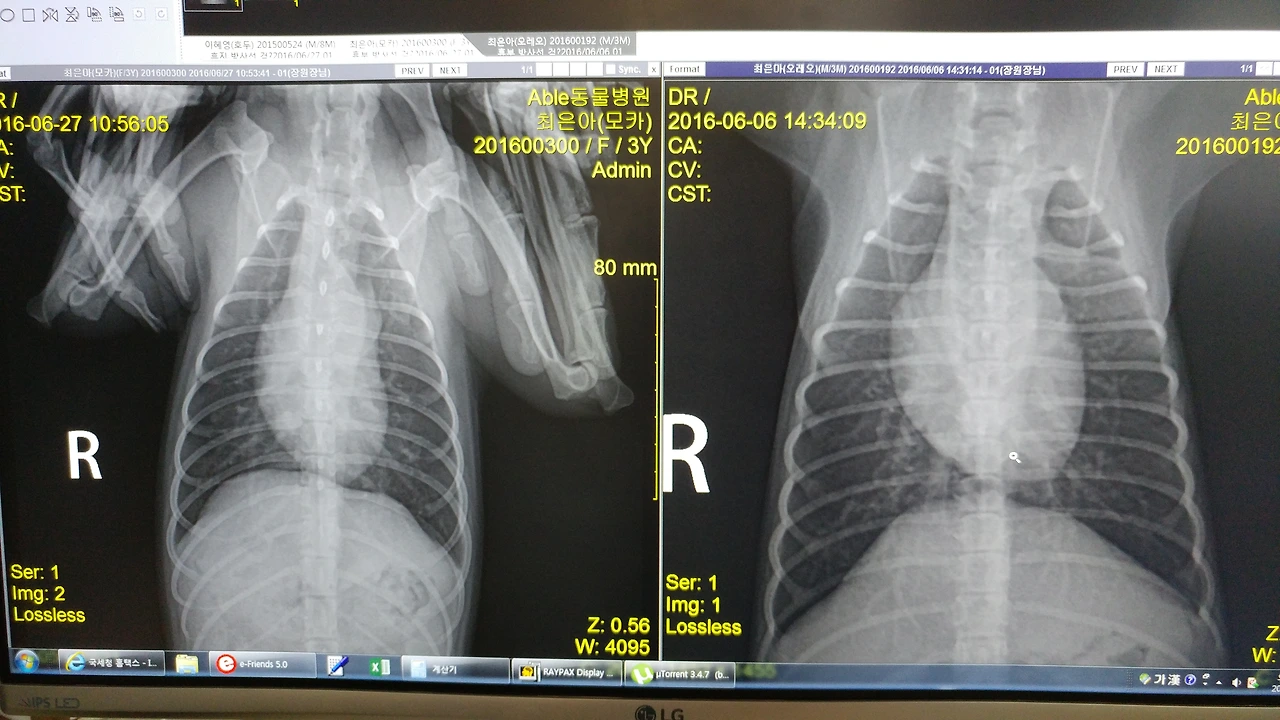

기관지 협착증에 약간의 심장 기형까지 있다고 했다.

2016년 왼쪽: 모카 / 오른쪽: 오레오